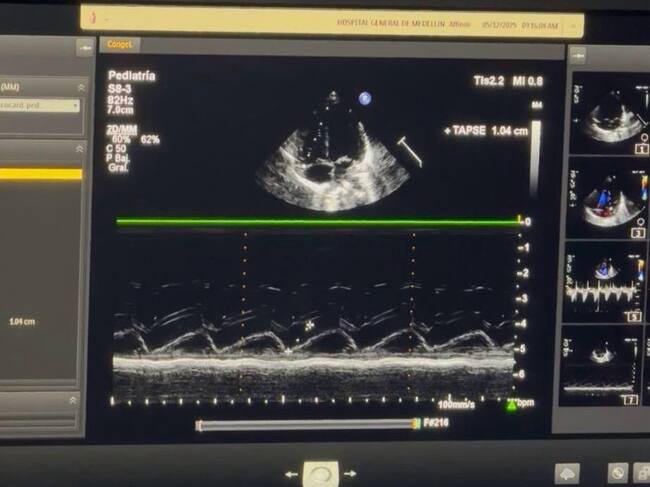

Foto: Caracol Radio.

El Hospital General de Medellín recibió este viernes un ecocardiógrafo pediátrico completamente nuevo, una donación de la Fundación Infantil Santiago Corazón que marca un hito en la detección temprana de cardiopatías congénitas en recién nacidos. Con este equipo, el centro asistencial podrá aumentar de manera significativa su capacidad diagnóstica.

El Hospital General, donde nacen más de 4.000 bebés al año, celebró la llegada del equipo, que además permitirá disminuir los costos operativos: anteriormente el centro debía alquilar un ecocardiógrafo a un costo anual de 120 millones de pesos, sin disponibilidad completa. Con el nuevo equipo propio, los exámenes podrán realizarse sin restricciones de tiempo ni trámites adicionales.